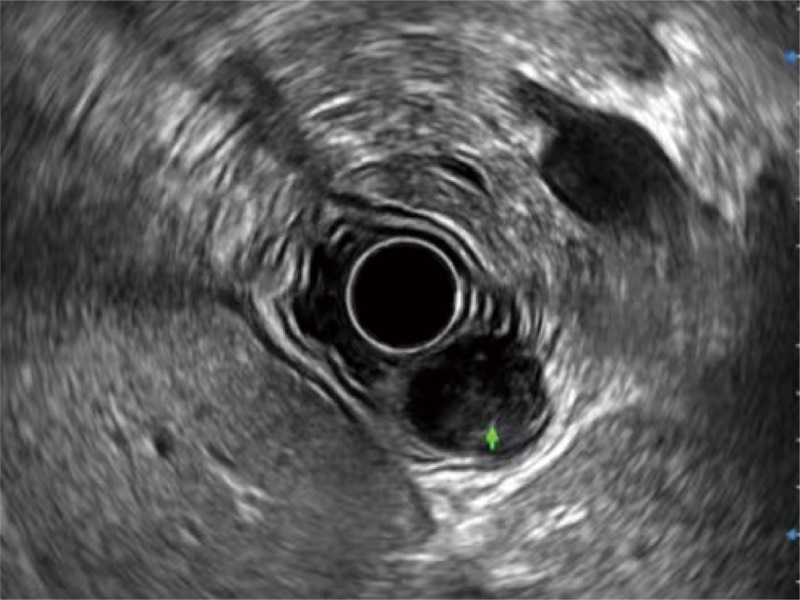

食管内间质瘤清晰显像

360°电子环形扫查与高清内镜影像相结合,提供了良好的插入性能和高清的内镜图像